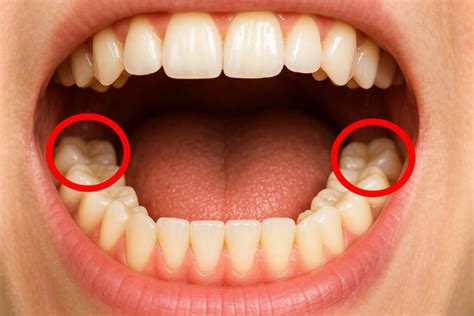

Estas muelas, conocidas como muelas del juicio, científicamente se llaman muelas cordales o terceros molares y son las últimas piezas definitivas en erupcionar. Aunque no salen a todo el mundo, las muelas del juicio son 4, 2 en el maxilar superior y 2 en la mandíbula.

Debido a la evolución genética, cada vez hay más personas que no llegan a desarrollar los terceros molares en su totalidad. Por este motivo, no tienen espacio suficiente en la cavidad bucal y pueden provocar malposiciones y apiñamiento dental.

- Apiñamiento con dientes cercanos: si los cordales no tienen suficiente espacio para salir correctamente, pueden apiñarse con los dientes adyacentes, dañándolos.

- Cordales retenidos: estos están completamente ocultos dentro de la encía. Las muelas del juicio ocultas pueden causar dolor, producido por infecciones, que dañan las raíces o los huesos de dientes contiguos. Además, pueden generar quistes o tumores de forma excepcional.

- Cordales parcialmente erupcionados: estos emergen de la encía a medias y, debido a la dificultad para mantener la higiene de la zona, se acumulan restos de alimentos y favorece la acumulación de bacterias, pudiendo provocar caries, abscesos de pus en la encía e incluso infecciones.

Muelas del juicio retenidas

Ya que no todos las dentaduras tienen el mismo tamaño y las mismas características, también existe la posibilidad de que las muelas del juicio se queden retenidas. Esto ocurre cuando en la boca no existe suficiente espacio para que crezcan de forma normal, de manera que crecen dentro de la encía y generar diversos problemas muy dolorosos.